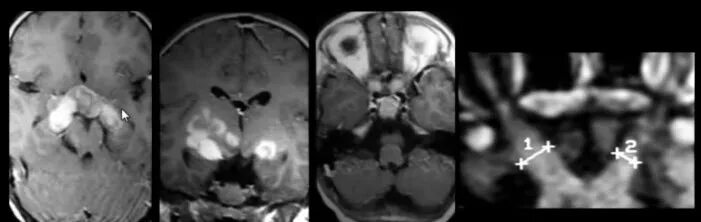

Нейрофиброматоз мрт